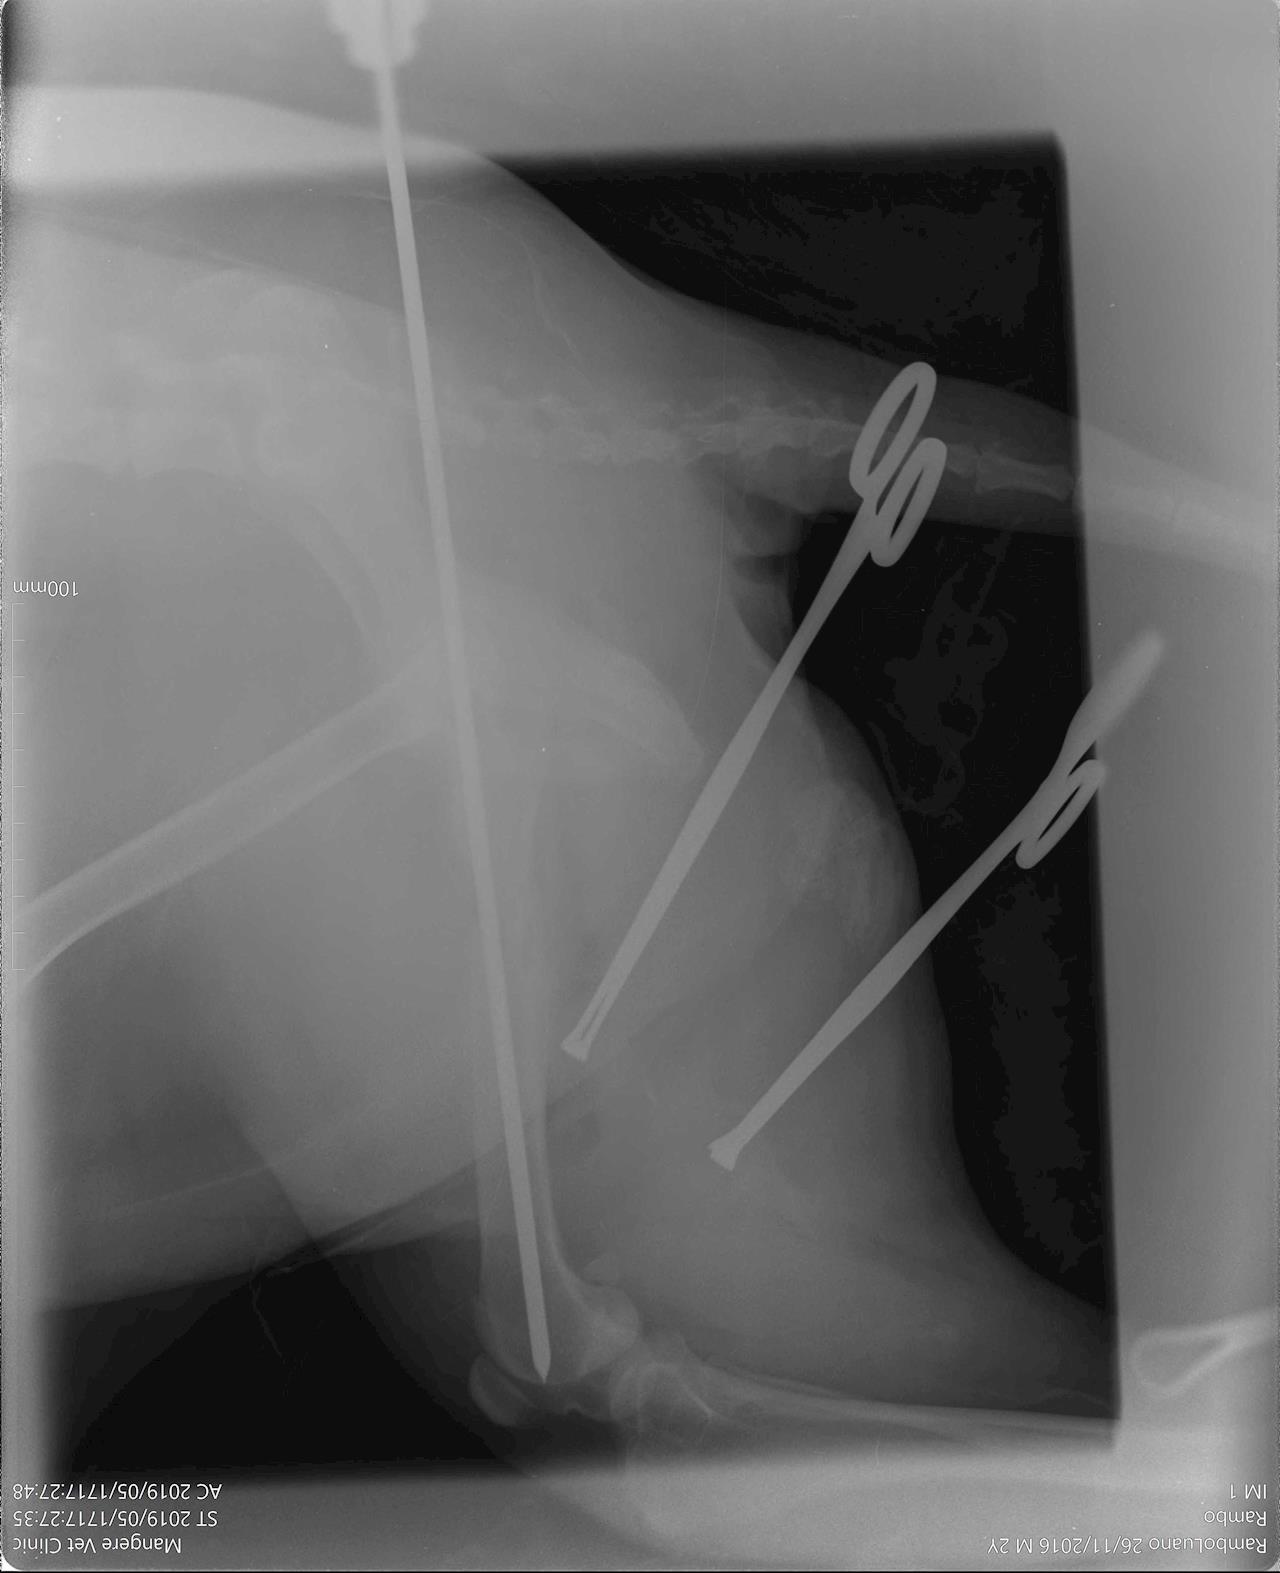

Rambo needs either pinning or, failing that, amputation. Both procedures are pricey but imperative in order to improve his quality of life.

The money will go towards the cost of Rambo's care, from either a pinning operation or possible amputation, to vet fees and medication.

Our Rambo is out of surgery!  18 May 2019

It went really well, I just got off the phone with the amazing team at Mangere Vet Clinic & Onehunga Vet and Pet Supplies who've done a brilliant job of fixing up our Ramby.

The cost of the surgery comes to $1,271.60 so we are very much on track to getting it together and getting him home. Some update pics from the vets 😭🙌 thanks again to every who has donated or shared, it means the world to us and of course to our Rambo (though he may not show it, unless you have treats).